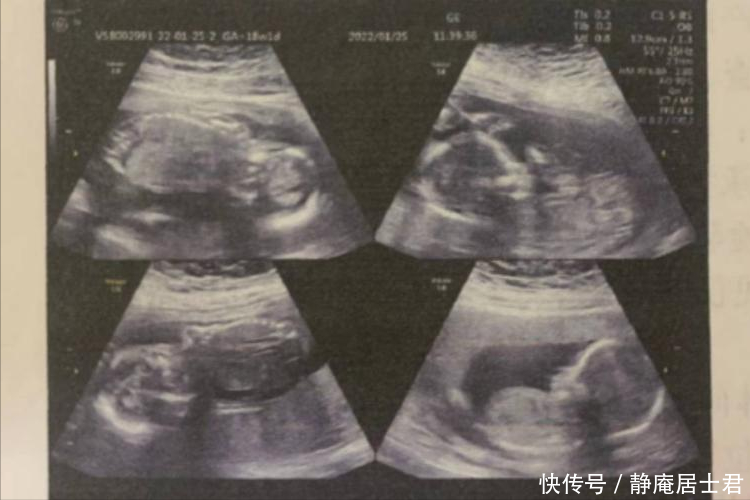

2003年,湖南一孕妇感觉自己怀孕,比其他孕妇的肚子大的多。到医院检查之后,才得知肚子里有四个宝宝。

怀孕差不多3个月的时候,易重江感觉自己的肚子异常的大。丈夫担心她有其他问题,带着她来到医院检查。

检查结果显示,易重江怀的是四胞胎。夫妻俩非常的开心,但听到医生接下来的话,又充满了担忧。